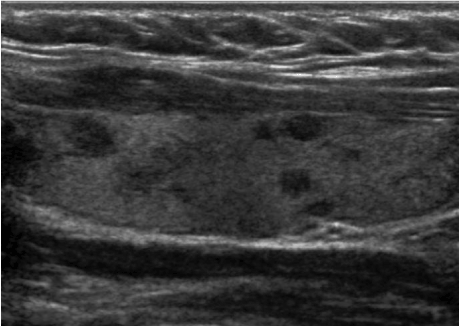

The patient is a 41-year-old female with a past medical history of Hashimoto thyroiditis who presented with new-onset palpitation, unintentional weight loss (approximately 10 lbs.), hair loss, fatigue, constipation and tremors over the past 5 months. On presentation, the patient vitals were: blood pressure 148/82 mmHg, heart rate 72 /min, respiratory rate 16 /min, temperature 37 °C and oxygen saturation of 98%. Initial laboratory results revealed TSH 0.02 ng/dL, T4 of 1.71 ng/dL, and T3 3.2 ng/dL which were significantly different from her baseline (TSH 3.73 ng/dL, T4 of 1.08 ng/dL, and T3 2.70 ng/dL). After initial evaluation, the patient's home levothyroxine (112 mg daily) was discontinued and she was started on propranolol (10 mg daily). From initial onset of hypothyroidism, she continued to be sero-negative for thyroperoxidase antibody. On the other hand, serology test was positive for thyroid stimulating antibodies, at 3.93 IU/L, diagnostic of Graves' disease. Her thyroid stimulating immunoglobin level was also 164 units. The ultrasonogram of her thyroid revealed a bilateral multinodular goiter and heterogeneous echotexture (Figure 1). On her radioactive studies, she had heterogeneous uptake. Radioiodine ablation was not possible due to her iodine allergy and the heterogeneous uptake within the gland. Thus, our patient underwent a total thyroidectomy. Pathological examination of removed thyroids revealed abundant thyroglobulin, consistent with the diagnosis of hyperthyroidism (Figure 2). She had uneventful postoperative recovery, but developed postoperative hypothyroidism. Her laboratory results were TSH 2.73 ng/dL, T4 of 0.74 ng/dL, and T3 2.70 ng/dL. As a result, the patient was started on levothyroxine (112 mg daily) and now remains symptom free.

Figure 1. Ultrasonogram of left thyroid demonstrates multiple nodules and heterogeneous echotexture.